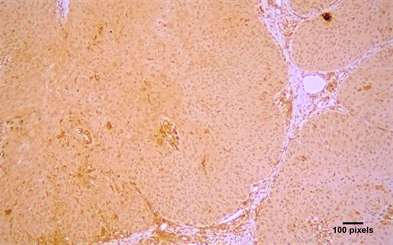

There was a tendency for increased expression of Arp2 and Arp 3 in invasive OSCC, compared to verrucous carcinomas (Figure 2) and carcinomas in situ

Figure 2. Immunohistochemical expression of Arp2 (+++) in a VSCC (streptavidin-biotin-peroxidase immunostaining, original magnification ×10).

(Figure 3), but this correlation was not statistically significant (Table 2). Finally, Arp2 and Arp3 expression was more common in well differentiated OSCC compared to moderate or poorly differentiated OSCC, but statistical significance between grade and expression was not seen (Table 4).